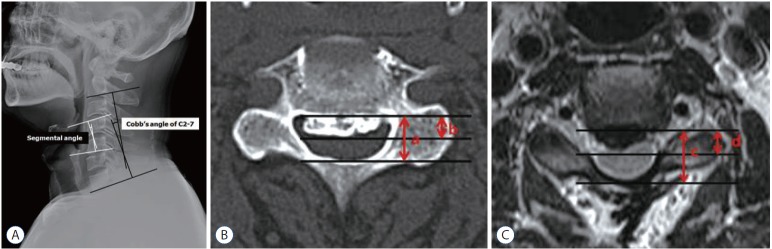

Radiologic evaluation (Fig. 1)

Fig. 1.

Cobb’s angle of the entire cervical curvature was measured as the angle between the lower margin of C2 and C7, and the segmental angle was defined and measured by Cobb’s method between the lines of the upper vertebral body’s upper margin and the lower vertebral body’s lower margin in the segment of interest on a static neutral position (A). Lordosis was recorded as a positive value, and kyphosis was recorded as a negative value. The ossification of the posterior longitudinal ligament (OPLL) occupying ratio was calculated as the maximum thickness of the OPLL to the anterior–posterior diameter of the spinal canal at the main OPLL lesion on computed tomography scan (b/a) (B). In case of loss of the anterior or posterior structure of the spinal canal at the main OPLL lesion during initial surgery, the boundary of the dural sac anteriorly or posteriorly on T2 weighted image was regarded as the extent of the diameter (d/c) (C).

Cobb’s angle of the entire cervical curvature was measured and defined as the angle between the lines passing through the lower margin of the C2 and C7 vertebral bodies. The segmental angle was defined and measured by Cobb’s method between the lines of the upper vertebral body’s upper margin and the lower vertebral body’s lower margin in the segment of interest. Cobb’s and segmental angles were measured in the lateral X-ray or lateral view of computed tomography (CT) scan in neutral position. Lordosis was recorded as a positive value, and kyphosis was recorded as a negative value.

The OPLL occupying ratio was calculated as the maximum thickness of the OPLL to the anterior-posterior diameter of the spinal canal at the main OPLL lesion on CT scan5,16). In case of loss of the anterior or posterior structure of the spinal canal at the main OPLL lesion during initial surgery, the boundary of the dural sac anteriorly or posteriorly on T2 weighted image was regarded as the extent of the diameter.